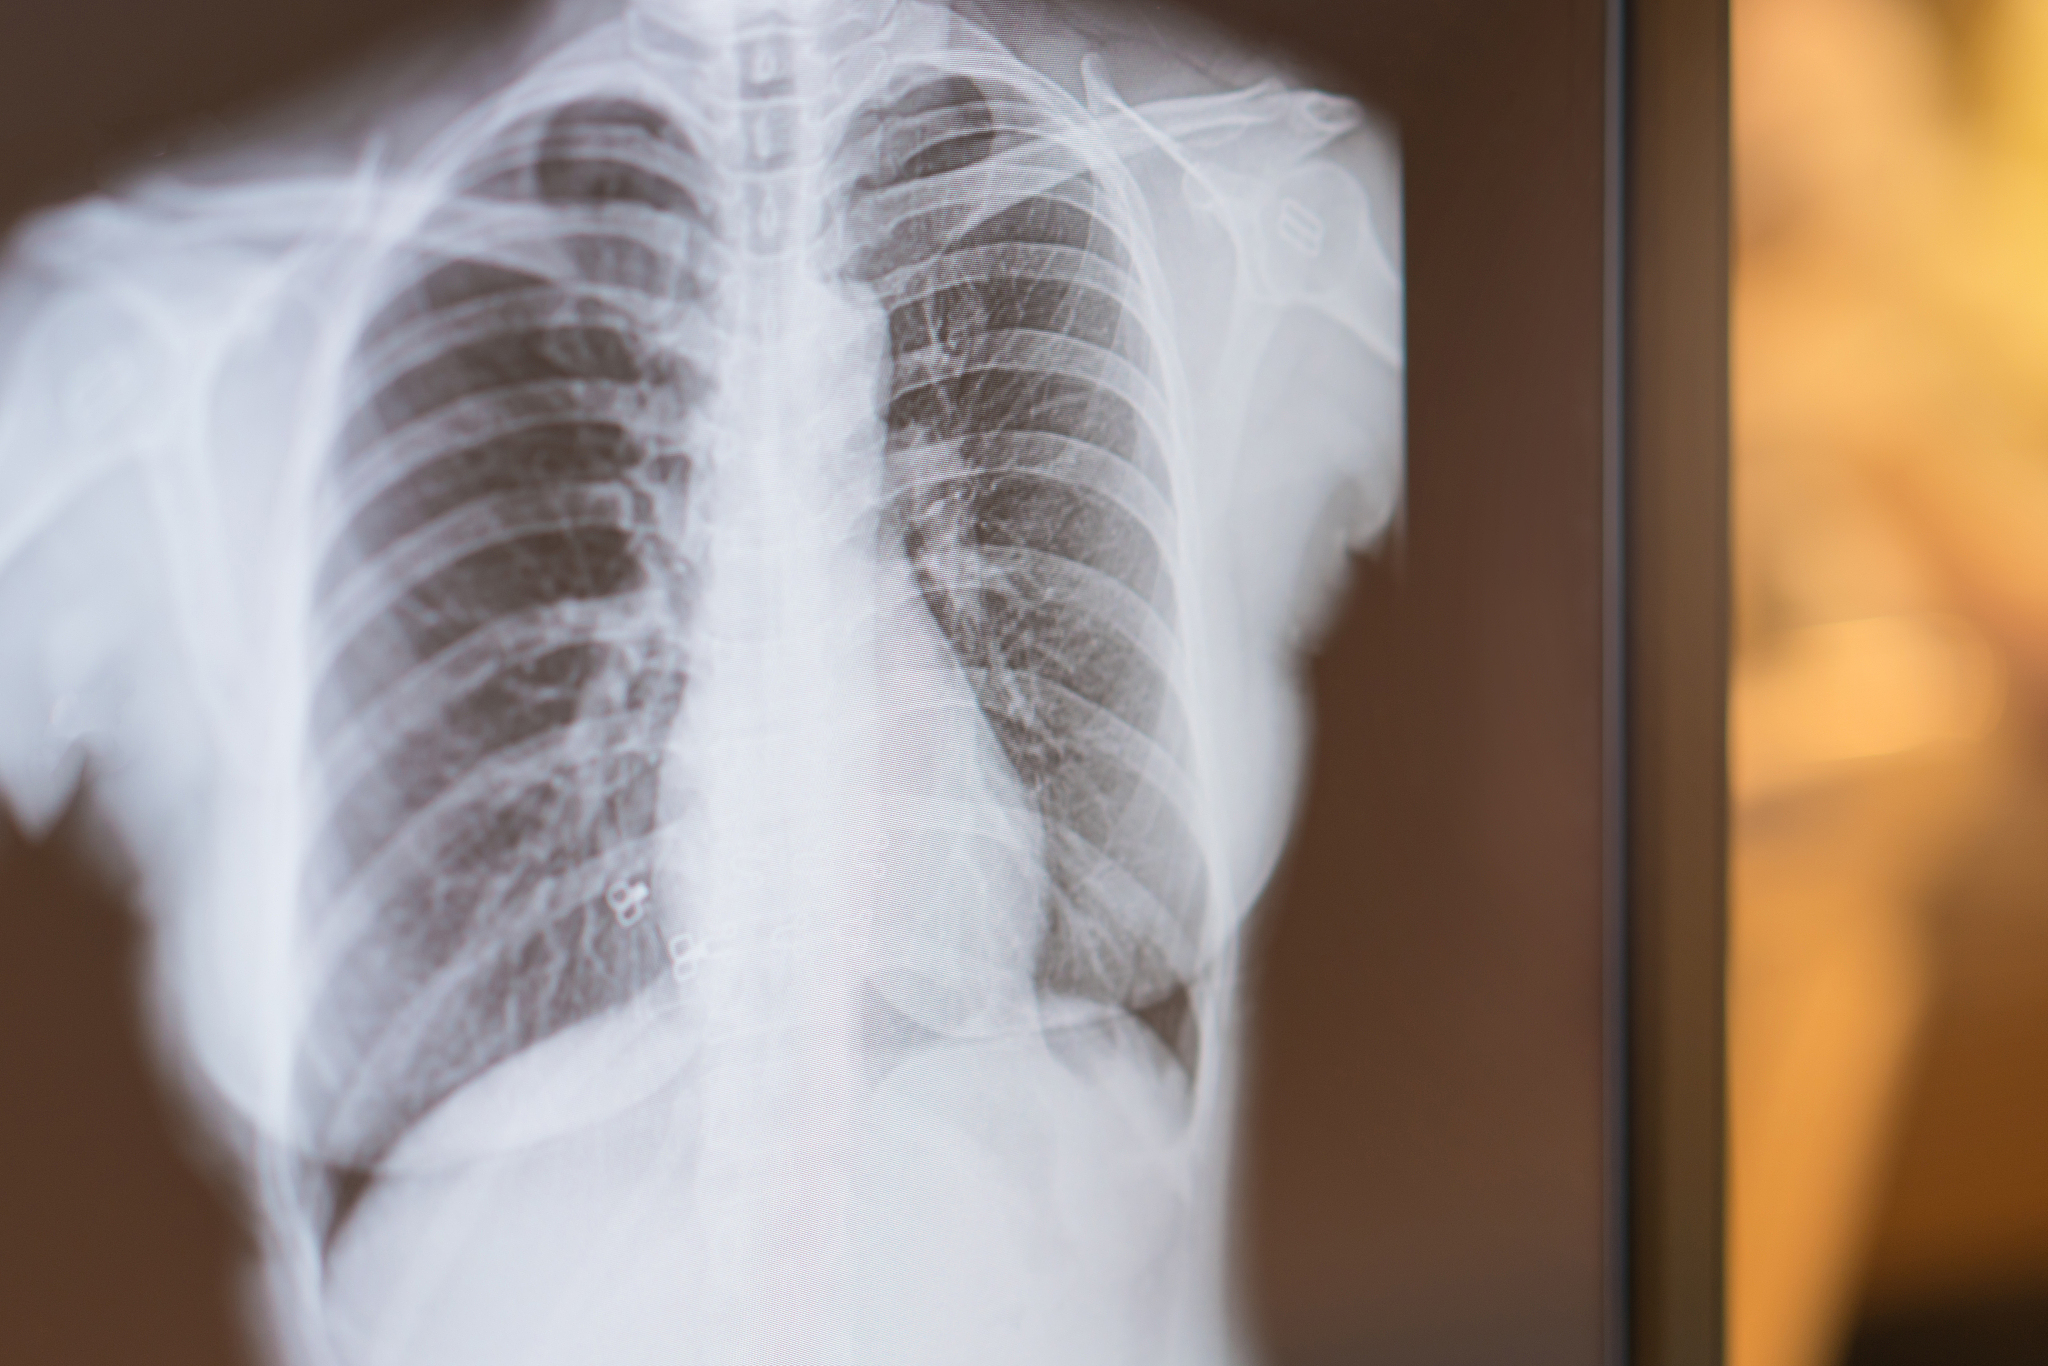

• 姓名:叶先生* 年龄:68岁* 主要症状:左侧肢体乏力2个月、咳嗽1个月、昏迷6小时

• 合并肺性脑病PS4分的晚期重症肺癌

患者入院前2个月出现左侧肢体乏力,并逐渐出现咳嗽、咳痰、发热等症状。在外院就诊,检查发现左肺肿块,考虑肺癌,并伴有颅内、淋巴结等多处转移。入院前6小时,患者出现意识模糊,逐渐进入昏迷状态。